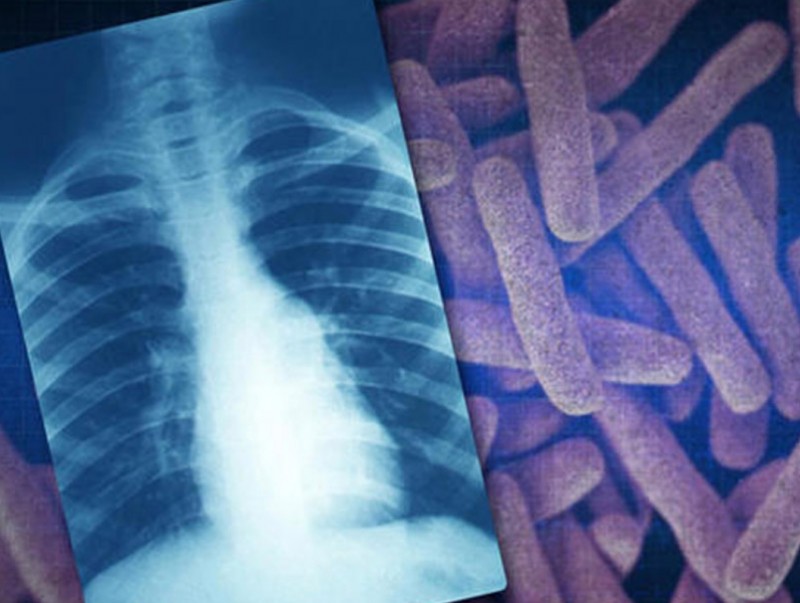

Иргэд сүреэгийн халдвартай эсэхээ үнэ төлбөргүй оношлуулж, эмчлүүлэх боломжтой

MNB Монголын Мэдээ суваг үзүүлж байна: Иргэд сүреэгийн халдвартай эсэхээ үнэ төлбөргүй оношлуулж, эмчлүүлэх боломжтой.